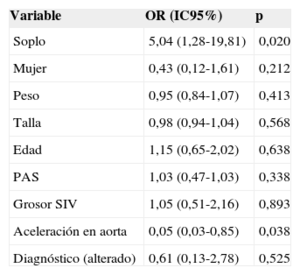

Análisis multivariable que muestra relación estadísticamente significativa de la presencia de falso tendón con el soplo y con la aceleración en la aorta

| Variable | OR (IC95%) | p |

|---|---|---|

| Soplo | 5,04 (1,28-19,81) | 0,020 |

| Mujer | 0,43 (0,12-1,61) | 0,212 |

| Peso | 0,95 (0,84-1,07) | 0,413 |

| Talla | 0,98 (0,94-1,04) | 0,568 |

| Edad | 1,15 (0,65-2,02) | 0,638 |

| PAS | 1,03 (0,47-1,03) | 0,338 |

| Grosor SIV | 1,05 (0,51-2,16) | 0,893 |

| Aceleración en aorta | 0,05 (0,03-0,85) | 0,038 |

| Diagnóstico (alterado) | 0,61 (0,13-2,78) | 0,525 |

FT: falso tendón del ventrículo izquierdo; IC95%: intervalo de confianza del 95%; OR: odds ratio; PAS: presión arterial sistólica; SIV: septo interventricular.

En el análisis multivariable, la OR ajustada (ORa) para la presencia de soplo es 5,05 (IC95%, 1,28-19,81), mientras que para la aceleración en la aorta descendente fue ORa = 0,05 (IC95%, 0,03-0,85), de manera que la presencia de FT se relacionó con menor velocidad en la aorta descendente (tabla 4).

Como en algunos estudios previos16–18, se demuestra relación estadísticamente significativa entre la presencia del FT visualizado en ecocardiografía y el soplo inocente infantil (p < 0,05). También se halló menor velocidad en la aorta descendente. No se observó ninguna otra relación con hallazgos de la ecocardiografía ni alteraciones en el electrocardiograma o clínica de los pacientes que se pudiera relacionar estadísticamente con la presencia del FT. Se han descrito múltiples asociaciones de la presencia de FT, con el origen de arritmias19,20,26, alteraciones valvulares21 o infecciones22, si bien no se ha demostrado claramente. Al igual que en este estudio, la relación más aceptada es con el soplo inocente infantil16–18. Dicho soplo se ha relacionado con aumento de la velocidad en la aorta28; en este estudio, lejos de ser un factor de confusión, se ve que la presencia de FT haría que dicha velocidad fuera menor. Quizá el movimiento producido por la salida de la sangre produzca un movimiento vibratorio del FT causante del soplo y al mismo tiempo una disminución de la sangre en la velocidad aórtica. Los factores de longitud del FT, grosor, volumen de eyección y tamaño del ventrículo izquierdo harían que en la edad infantil se dieran los factores idóneos para su presencia.